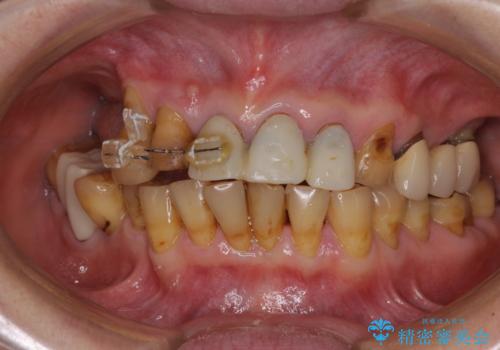

- 前歯の部分矯正や仮歯に置き換えるなど、治療途中のまま放置してしまったとのことで来院された患者様です。

骨格的に下顎骨が前方にあり、歯列の幅も下顎の方が大きいため、奥歯に負担のかかりやすい咬合でした。

大臼歯部は、上下左右ともに咬合により問題が生じており、骨格的な問題から積極的な治療をするべきか判断の難しい状況でした。